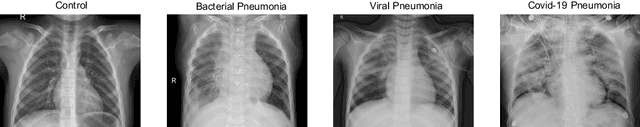

Abstract:The ongoing crisis of the COVID-19 (Coronavirus disease 2019) pandemic has changed the world. According to the World Health Organization (WHO), 4 million people have died due to this disease, whereas there have been more than 180 million confirmed cases of COVID-19. The collapse of the health system in many countries has demonstrated the need of developing tools to automatize the diagnosis of the disease from medical imaging. Previous studies have used deep learning for this purpose. However, the performance of this alternative highly depends on the size of the dataset employed for training the algorithm. In this work, we propose a classification framework based on sparse coding in order to identify the pneumonia patterns associated with different pathologies. Specifically, each chest X-ray (CXR) image is partitioned into different tiles. The most relevant features extracted from PCA are then used to build the dictionary within the sparse coding procedure. Once images are transformed and reconstructed from the elements of the dictionary, classification is performed from the reconstruction errors of individual patches associated with each image. Performance is evaluated in a real scenario where simultaneously differentiation between four different pathologies: control vs bacterial pneumonia vs viral pneumonia vs COVID-19. The accuracy when identifying the presence of pneumonia is 93.85%, whereas 88.11% is obtained in the 4-class classification context. The excellent results and the pioneering use of sparse coding in this scenario evidence the applicability of this approach as an aid for clinicians in a real-world environment.

Abstract:Respiratory diseases kill million of people each year. Diagnosis of these pathologies is a manual, time-consuming process that has inter and intra-observer variability, delaying diagnosis and treatment. The recent COVID-19 pandemic has demonstrated the need of developing systems to automatize the diagnosis of pneumonia, whilst Convolutional Neural Network (CNNs) have proved to be an excellent option for the automatic classification of medical images. However, given the need of providing a confidence classification in this context it is crucial to quantify the reliability of the model's predictions. In this work, we propose a multi-level ensemble classification system based on a Bayesian Deep Learning approach in order to maximize performance while quantifying the uncertainty of each classification decision. This tool combines the information extracted from different architectures by weighting their results according to the uncertainty of their predictions. Performance of the Bayesian network is evaluated in a real scenario where simultaneously differentiating between four different pathologies: control vs bacterial pneumonia vs viral pneumonia vs COVID-19 pneumonia. A three-level decision tree is employed to divide the 4-class classification into three binary classifications, yielding an accuracy of 98.06% and overcoming the results obtained by recent literature. The reduced preprocessing needed for obtaining this high performance, in addition to the information provided about the reliability of the predictions evidence the applicability of the system to be used as an aid for clinicians.